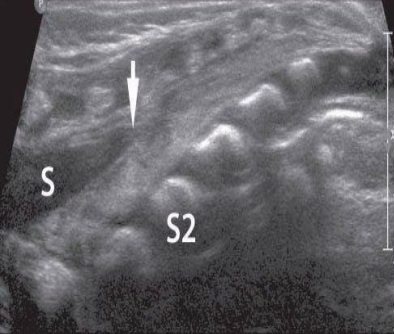

s

thecal sac

white arrow

end of thecal sac (about s2)

partially calcified coccyx

r

rectum filled with air